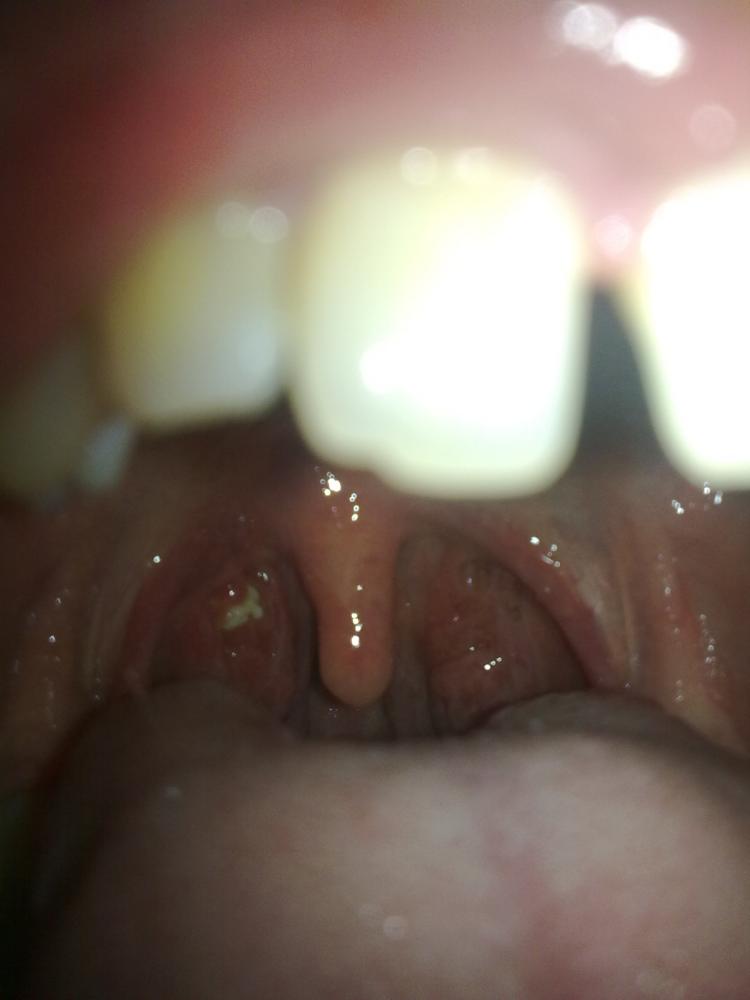

Ist Das In Meiner Mund Hohle Normal Habe Das Schon Langer Und Habe Manchmal Mandel Und Hals Schmerzen Und Spucke Manchmal Kleine Mandel Steinen Danke Mandeln Mundhohle

Das Gefühl einen Fremdkörper im Hals zu haben ohne dass dies tatsächlich der Fall sei wird nach Angaben des Arztes als Globus-Syndrom bezeichnet. Die Betroffenen haben das Gefühl dass das Essen im Hals stecken bleibt und trinken oft damit der Speisebrei weiterrutschen kann. Manchmal bilden sich Essensreste im Rachen die sind dann irgendwie weiß und zu Klümpchen geformt.

Sind Berührungen am Hals für Sie eher. Das Gefühl einen Fremdkörper im Hals zu haben ohne dass dies tatsächlich der Fall sei wird nach Angaben des Arztes als Globus-Syndrom bezeichnet. Sind Berührungen am Hals für Sie eher. Kannst ja selber mal schauen im Spiegel und abtasten zuindest wenn du da unempfidlich bist. Zunächst treten sie vor allem bei fester Nahrung auf. Verspüren Sie ein Gefühl als hätten Sie einen Kloss im Hals Globusgefühl Stört es Sie wenn Sie hochgeschlossenen Kleidungsstücke oder geschlossene Hemdkragen tragen. Höhe Schilddrüse jetzt irgendwelche Essensreste ansammeln oder dass da etwas gewachsen ist dass das Essen nur schwer durch lässt. Haben Sie bei einer bestimmten Kopfhaltung oder bei körperlicher Anstrengung das Gefühl keine Luft zu bekommen. Kannst sie ja mit ner Pinzette oder nem Zahnstocher rausstochern wenn du vorsichtig genug bist.

So haben sie während des Schluckens das Gefühl dass ihnen das Essen im Hals stecken bleibt und trinken dementsprechend nach. Seitdem habe ich es immer wieder dass ich das Gefühl habe mir bleibt das Essen im Hals stecken. Heay ich hab immer Essenreste im Hals die sind so 05cm groß und die gehen auch NIE runter egal was ich esse. Ich zerkaue bewusst meine Nahrung extrem und trotzdem bleibt Etwas stecken. Jedoch müssen weiße Stippen im Hals nicht immer gleich darauf schließen. Kannst sie ja mit ner Pinzette oder nem Zahnstocher rausstochern wenn du vorsichtig genug bist. Gefühl essensreste im hals Achalasie.